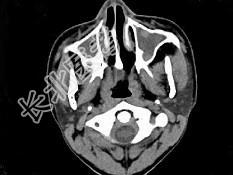

- 单项选择题男,14岁, 持续性鼻塞、嗅觉减退,流脓涕数年, CT检查如图,最可能的诊断为 ( )

A、鼻炎及鼻窦炎

B、鼻及鼻窦息肉

C、过敏性鼻炎及鼻窦炎

D、恶性肉芽肿

E、上颌窦癌